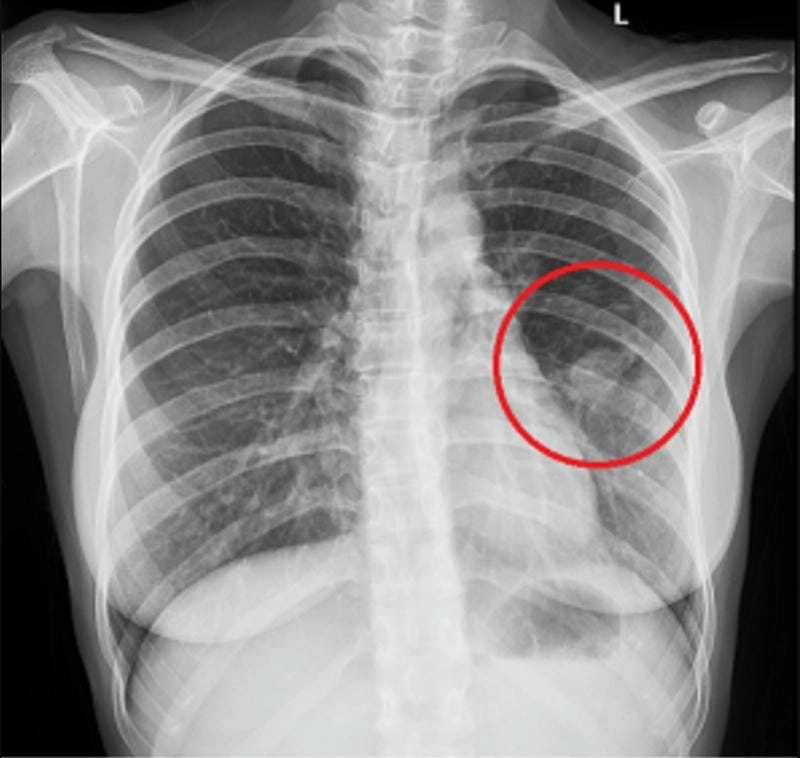

Hình ảnh bệnh lao phổi là tài liệu tham khảo quan trọng giúp người bệnh và bác sĩ dễ dàng nhận biết dấu hiệu bất thường. Việc quan sát hình ảnh X-quang, CT phổi giúp chẩn đoán chính xác mức độ tổn thương và đưa ra phương án điều trị kịp thời.

Bạn sẽ phải rùng mình khi chiêm ngưỡng hình ảnh bệnh lao phổi là như thế nào dưới ống kính y học thực tế. Những bức ảnh chụp X-quang cho thấy phổi bị tổn thương nặng, xuất hiện những đốm trắng mờ như bóng ma ám ảnh. Không chỉ là các tổn thương vật lý, đây còn là những “chứng tích sống” của căn bệnh âm thầm hủy hoại cơ thể qua từng hơi thở. Từ viêm nhẹ đến tổn thương lan rộng, hình ảnh bệnh lao phổi khiến người xem không thể rời mắt vì mức độ nghiêm trọng mà nó thể hiện rõ ràng qua từng chi tiết.

Cảnh báo: tổng hợp ảnh bệnh lao phổi chân thực này không dành cho người yếu tim. Đây là loạt hình ảnh y khoa được các chuyên gia sưu tầm và xác thực, ghi lại quá trình tiến triển của bệnh từ giai đoạn đầu đến giai đoạn nguy kịch. Từng mảng mô phổi bị ăn mòn, xơ hóa, hoại tử được phơi bày rõ nét dưới ánh sáng X-quang lạnh lùng. Những hình ảnh này không chỉ mang tính chất minh họa y học, mà còn là hồi chuông cảnh tỉnh cho bất kỳ ai còn lơ là với căn bệnh nguy hiểm này.

Thông qua những hình ảnh bệnh lao phổi thực tế, người đọc có thể hiểu rõ hơn về diễn biến của bệnh. Việc theo dõi hình ảnh giúp phát hiện sớm, điều trị đúng cách và ngăn ngừa biến chứng nghiêm trọng có thể xảy ra trong tương lai.